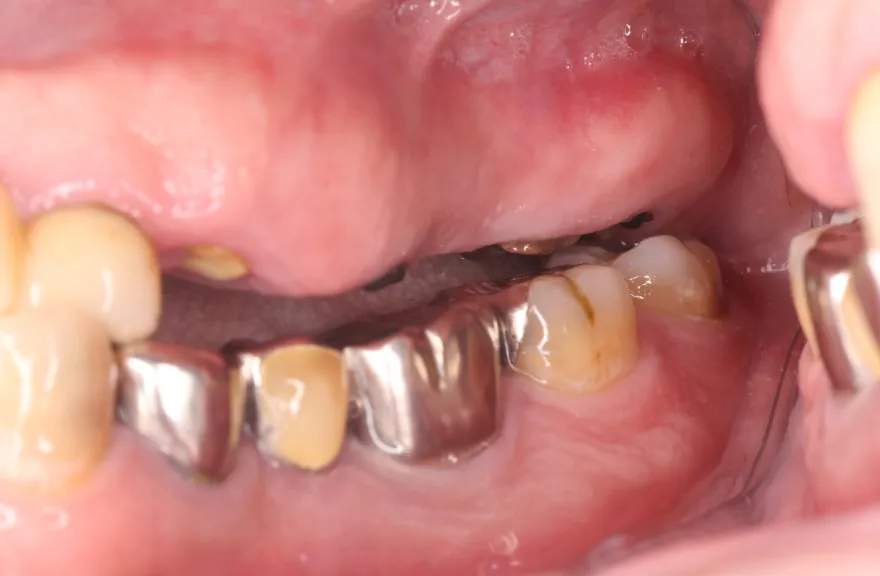

骨格の前後的な差がある方でした。術前のレントゲンより、上下で歯牙の損傷に明らかな差があるのがみてとれます。

上の歯がないところにインプラント治療を行い、上顎は全てインプラントフィクスチャーによる固定性の歯を入れられることも費用的には可能な方でした。

骨格的な前後差を考慮することなく歯をいれても、装着した人工物は決して長持ちしません。

今回の症例では、敢えて上顎は総義歯形態をとり、骨格的な前後の差を解消するよう工夫しました。

上顎の残っていた歯も、差し歯としては使えずとも、敢えて根だけ残すことによって組織を温存し、義歯の安定に寄与するよう設計しました。

ここまで全体的にしっかり治療しておけば、今後の人生においてトラブルになるようなことにはならないでしょう。 - 治療のリスク

下顎のクラウン・ブリッジは、丁寧な形成・印象処置と自費専門の技工士によって製作されたもので、虫歯による損傷が今後起こりにくいとは考えますが、定期的なメンテナンスは必須であり、生涯もつものではありません。

神経のない歯(失活歯)は神経がある歯に比べて力が大きくかかりやすく、根が割れたりするリスクがあります。割れ方にもよりますが、基本的には歯が割れてしまうと抜歯処置を行わなければならないことがほとんどです。